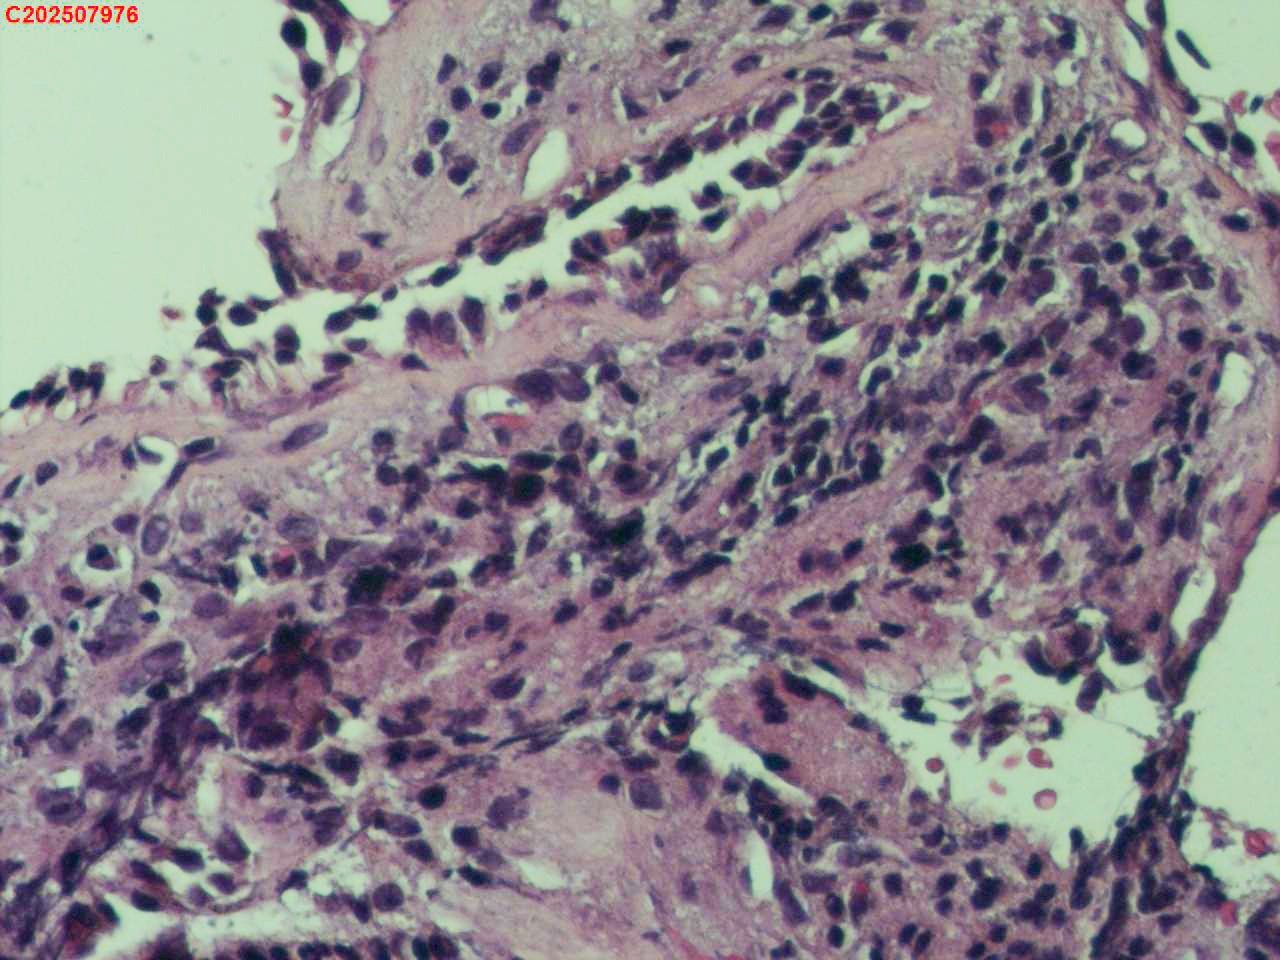

右肺上叶开口处 气管镜咬检

性别

男

年龄

65岁

临床诊断

一般病史

肺TB

标本名称

大体所见

右肺上叶开口上缘处可见肉芽增生,予咬检。

感觉:炎性纤维组织增生